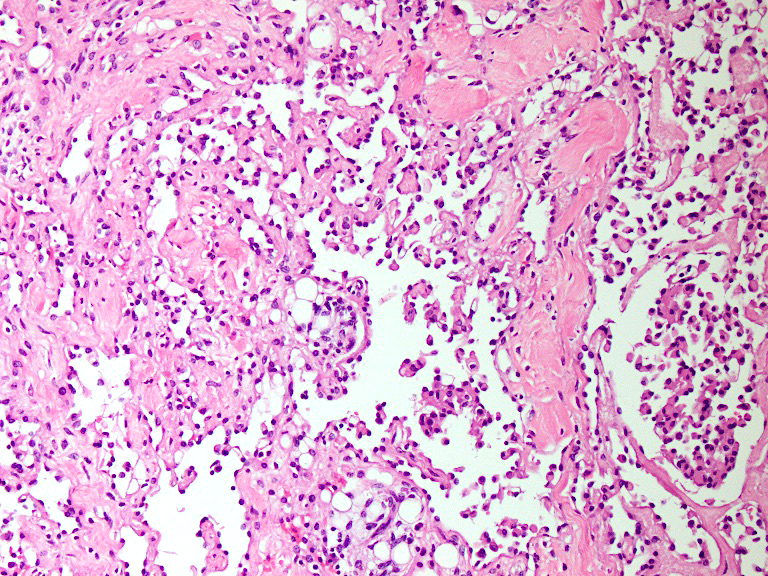

Microscopic (histologic) description

- Composed of elongated arborizing vascular channels that resemble rete testis, hence the name

- Endothelial cells are bland with hobnailed hyperchromatic nuclei

- Lesional stroma is fibrotic and shows lymphoid infiltrate (J Med Case Rep 2021;15:69, Int J Clin Exp Pathol 2010;3:528)

- In the dermis, vessels may become ectatic and lose retiform appearance

Microscopic (histologic) images